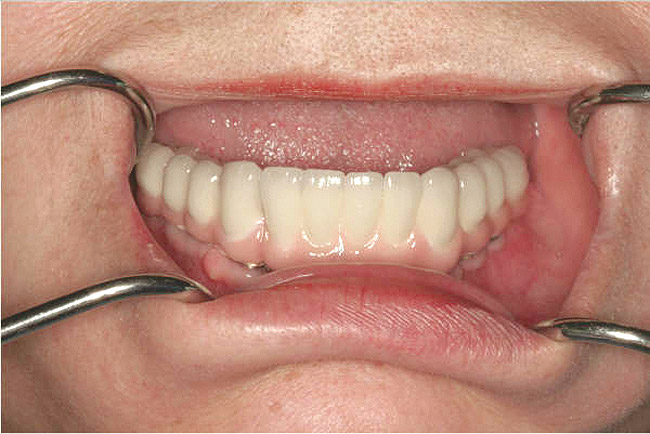

Figure 10c  Traditional fixed prosthodontics performed to level the opposing arch and regain sufficient crown height space.

Figure 10c

Figure 10d  Traditional fixed prosthodontics performed to level the opposing arch and regain sufficient crown height space.

Figure 10d